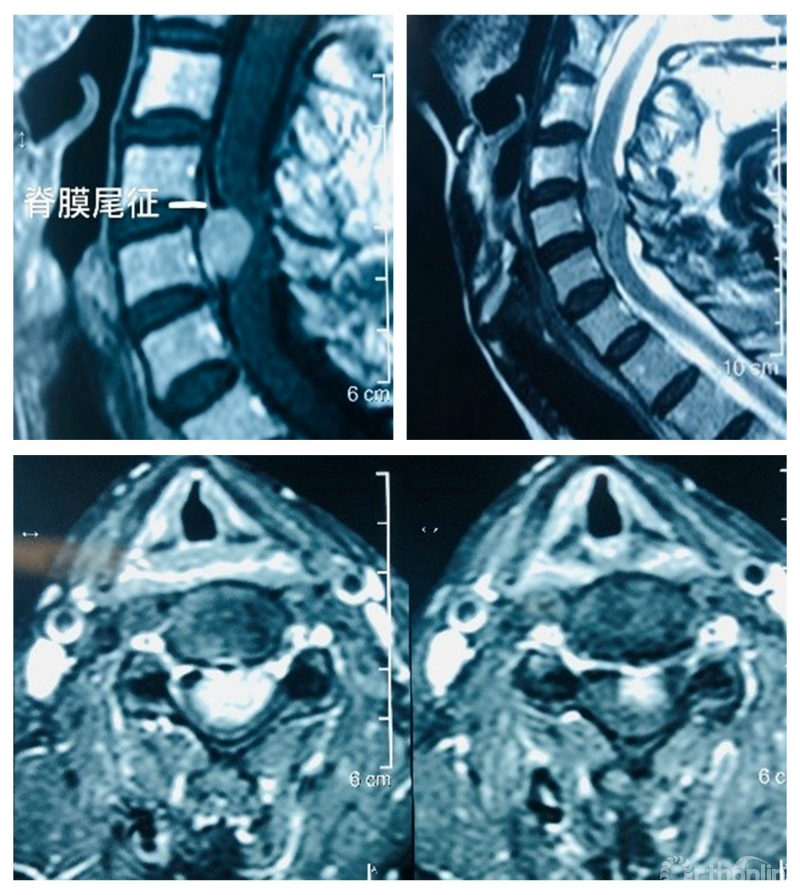

核磁共振显示:第5颈椎后部椎管内硬膜下脊髓腹侧脊膜瘤伴脊髓压迫。脊膜尾征明显。肿瘤最大侵占椎管达90%。术前横断面增强核磁共振显示肿瘤高度压迫脊髓。

术前影像学检查

诊断:颈椎脊髓腹侧脊膜瘤。